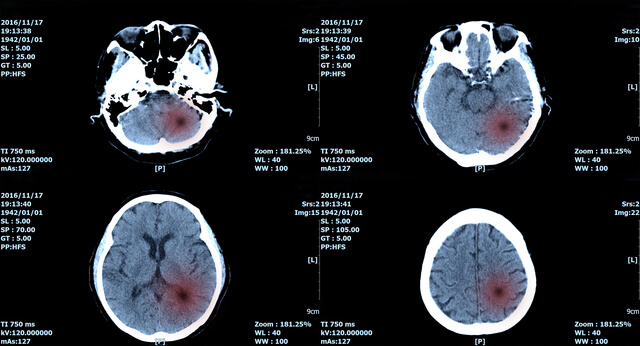

何が原因で高次脳機能障害が残っているのかをはっきりさせる必要があり、脳の画像などを見て正しく判断しなければなりません。

MRIやCTなどによる脳の検査で障害が残っているとわかる、明らかに記憶障害などに異常が現れているときは、高次脳機能障害の認定を受けることができます。

診察で、交通事故でどのような傷を受けたのか、MRIやCT、脳波検査などによって判断していきます。

それと同時に、身体に現れている症状についても照らし合わせていきます。

後遺障害診断書を提出し等級認定を受けるためには、症状や診断名(病名など)の記載、脳の画像、一定期間意識や記憶障害が現れたという内容を細かく書いてもらうことが重要です。